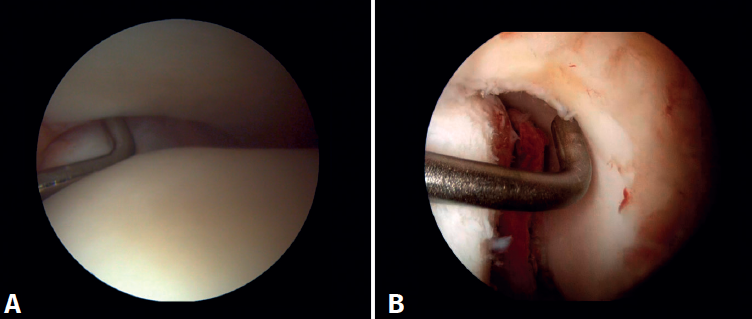

Figura 5. A: visión anterior del receso medial del tobillo; B: con el palpador tensamos las fibras del ligamento tibiotalar profundo.

Figura 6. Maniobras para evidenciar inestabilidad ligamentosa. A: lesión de la sindesmosis que permite la introducción del palpador en la tibioperonea distal; B: lesión del deltoideo que permite la introducción del palpador en el espacio medial tibioastragalino.